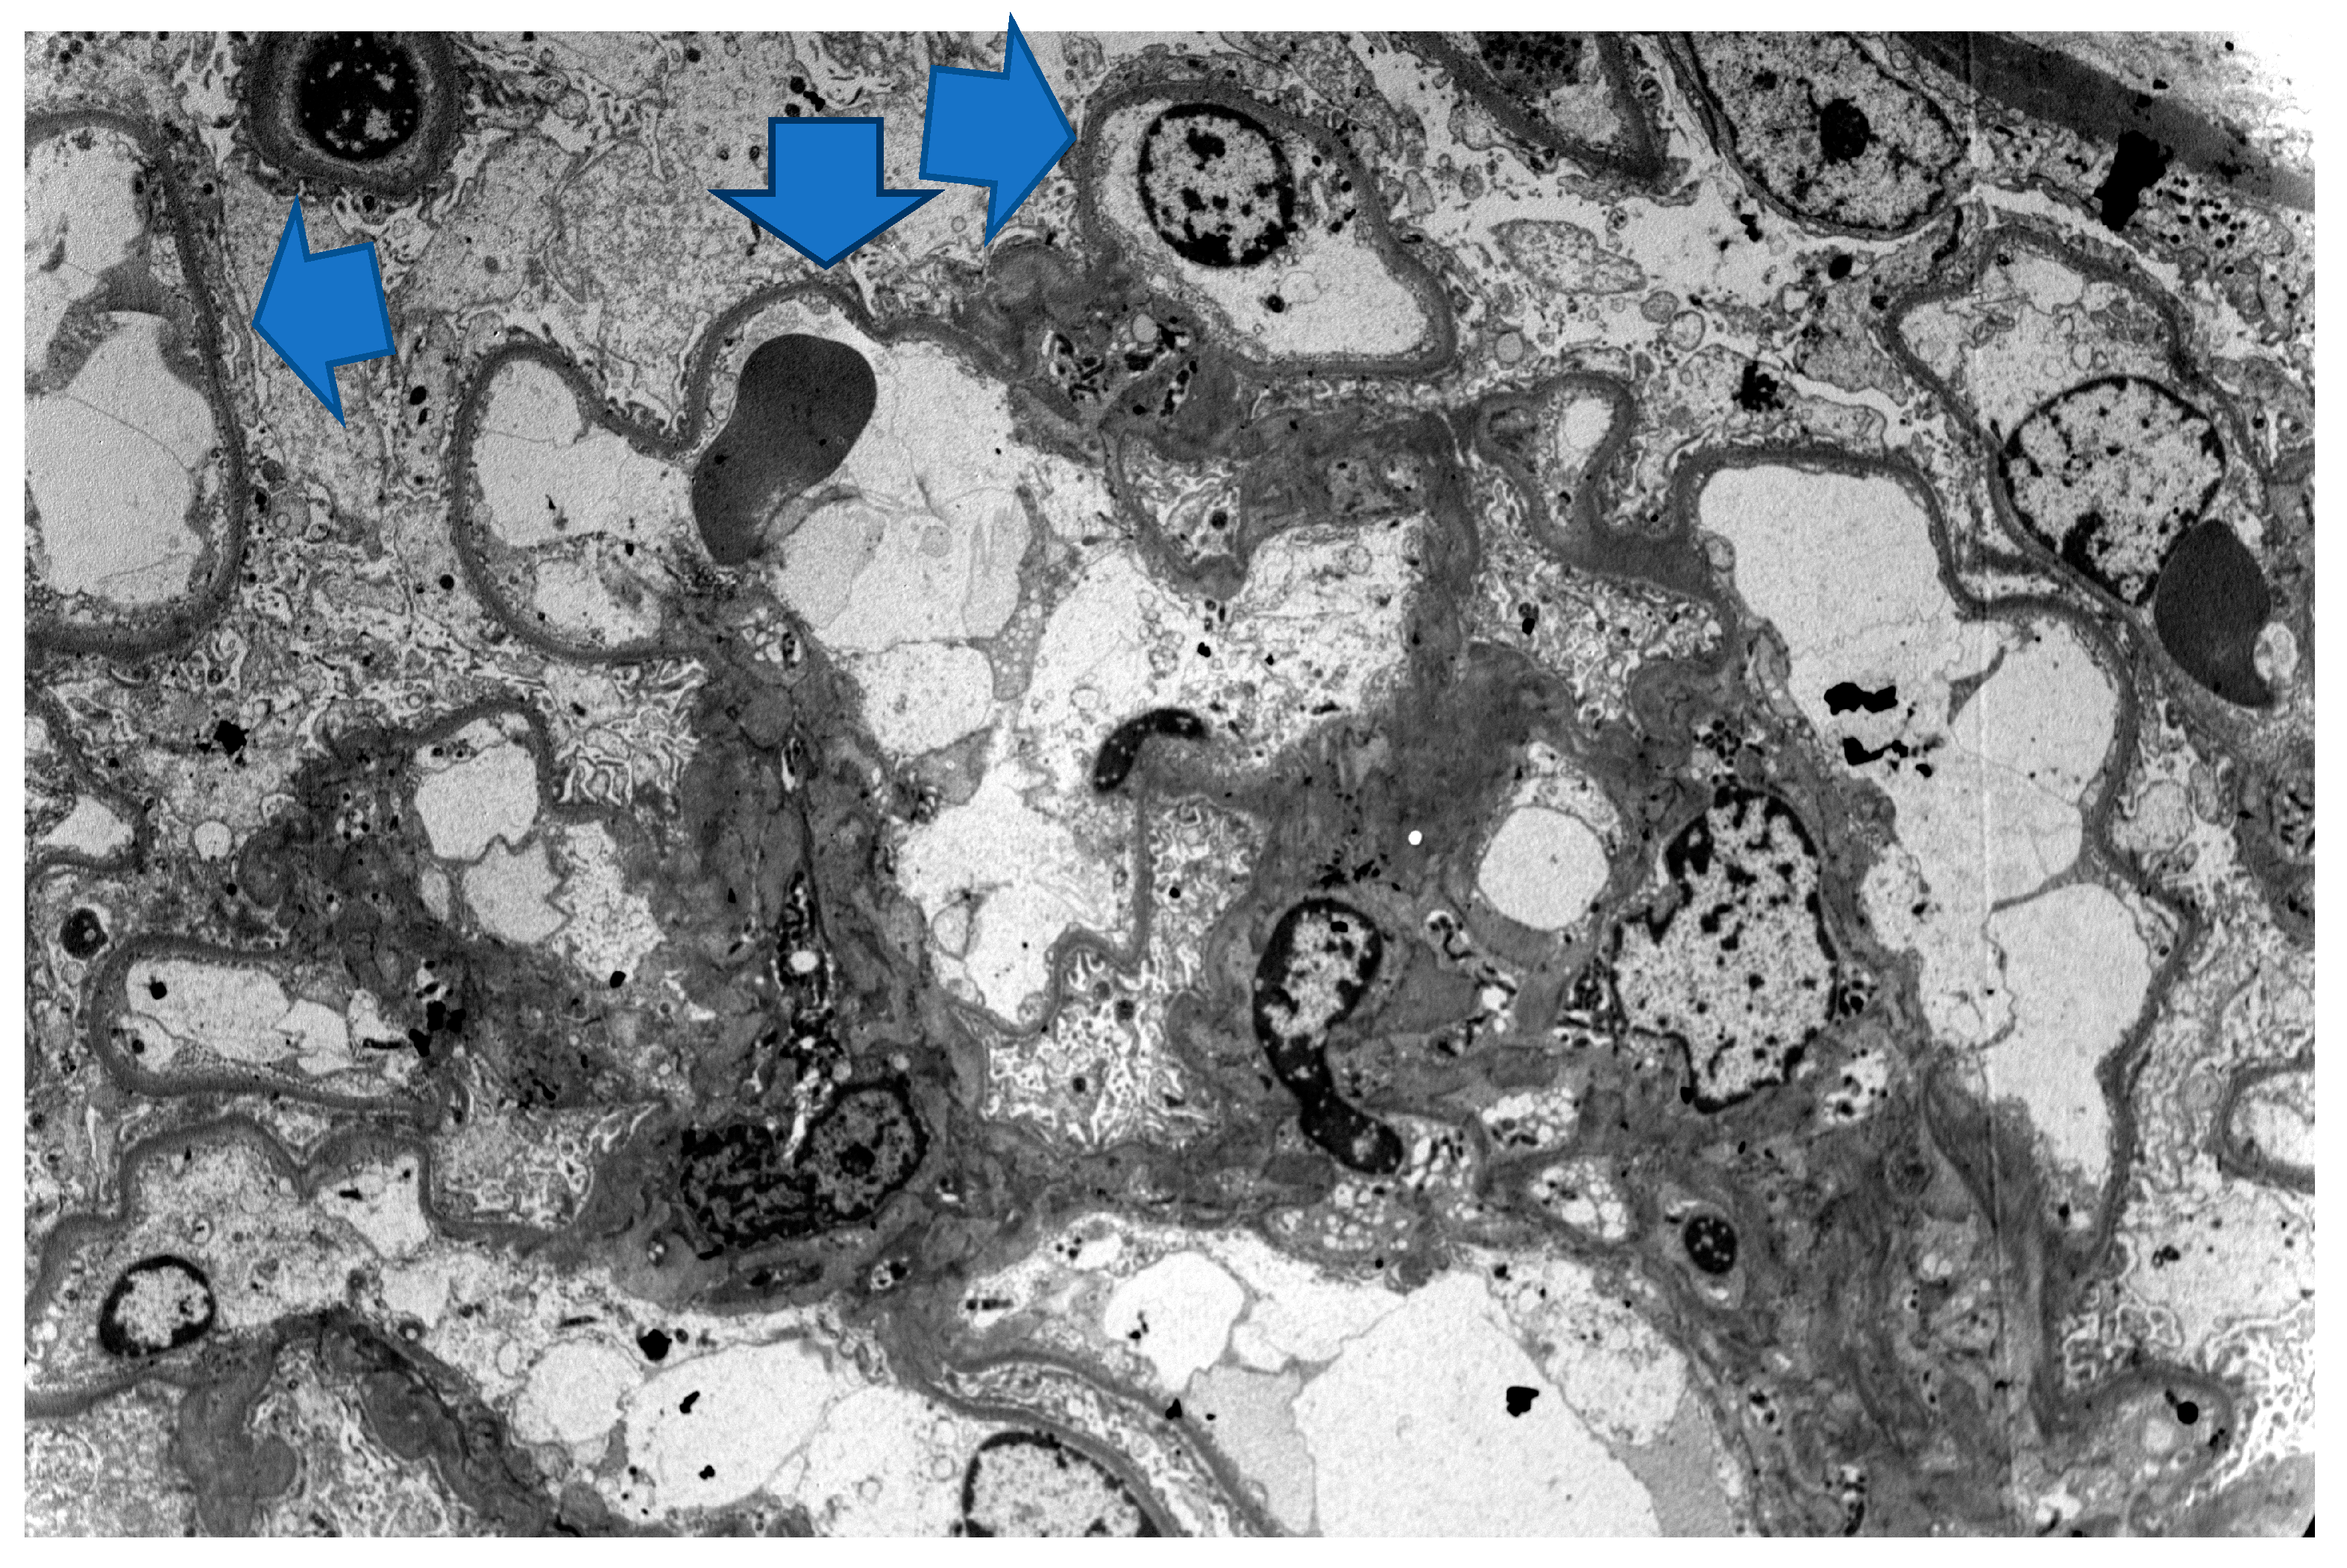

3. Case 2 Description: MCD Associated with D-Penicillamine

4. Case 3 Description: D-Penicillamine-Associated MCD

5. Case 4 Description: Pembrolizumab-Axitinib-Induced MCD